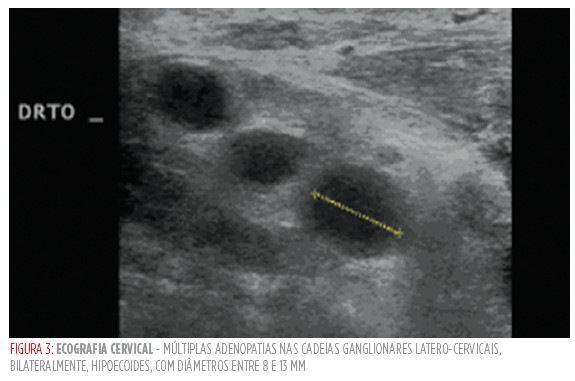

A doente foi internada no serviço de medicina interna para estudo etiológico de febre e quadro constitucional. Foram realizadas hemoculturas que se apresentaram negativas, pesquisa de anticorpos do VIH cujo resultado foi negativo e serologias para cmV, ebV e Vhs cujo resultado revelou, para todas, igg positividade. A ecografia cervical mostrou múltiplas adenopatias nas cadeias ganglionares latero-cervicais bilaterais, sugestivas de lesões secundárias (Fig 3). A tomografia computorizada tóraco-abdomino-pélvica não revelou massas ou adenomegalias noutras localizações. Perante as hipóteses diagnósticas de adenopatidas cervicais a doente realizou o teste igrA que foi positivo. O diagnóstico de tuberculose ganglionar foi confirmado após revisão da peça de biopsia excisional.